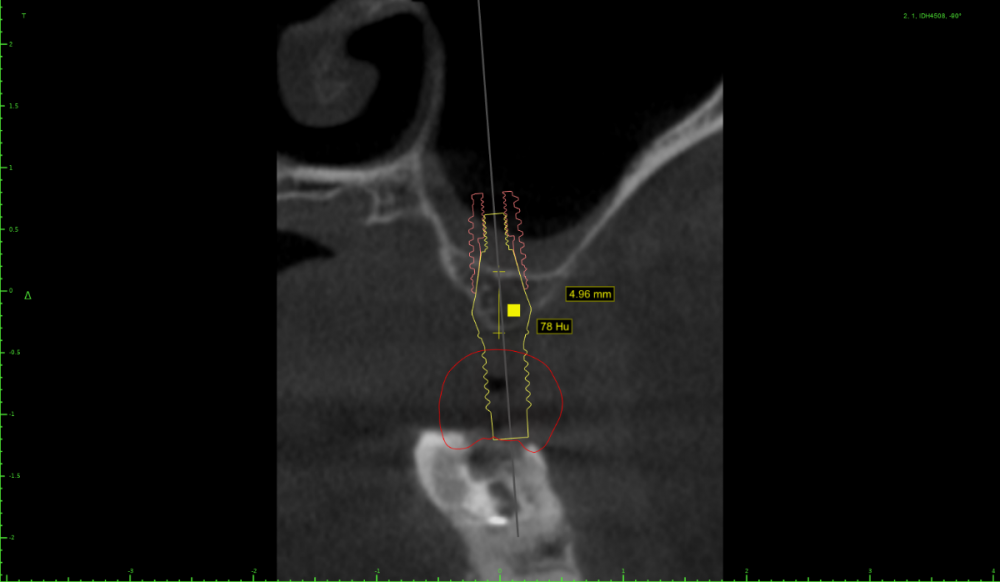

Женька Опубликовано 15 июля, 2022 Поделиться Опубликовано 15 июля, 2022 Коллеги, здравствуйте. Планирую небольшую НКР совместно с ОСЛ в боковом отделе верхней челюсти справа. Вот скрины. На реформате 3д план. Пожалуйста, поделитесь правильно ли мной выбран дизайн лоскута и фиксация мембраны (мембрана будет Creos, кость ауто+ксено (возможно ещё немного алло) p.s вариант обойтись без пластики не предлагать.)) Правильной ортопедической позиции добиться без нкр не выходит, кмк. Да и надо же пробовать как-то. Ссылка на комментарий

stommm Опубликовано 16 июля, 2022 Поделиться Опубликовано 16 июля, 2022 Если уж делать так, то я бы продлил разрез дальше, за 7. Удобнее мобилизовать, ну и медиальный сдвиг лоскута можно сделать. Мембрана 20х30. Дистальный пин на уровне 17, медиальный между 13 и 12. В области синуса пиниться стоит аккуратнее, можно провалиться, по этой же причине не стоит увлекаться работой со скребком в предполагаемой зоне фиксации мембраны. П.с. Померьте расстоянием между коронками. По наклону 17 есть ощущение что места маловато. Иногда в таких случаях проще поставить вертикально 16 ,15 с консолью 14, а не дистально наклонять апексы 16 и 14 1 Ссылка на комментарий

колесников Опубликовано 17 июля, 2022 Поделиться Опубликовано 17 июля, 2022 Во первых: у вас нет потери вертикального объёма,гребень практически в зените-это хорошо. Во вторых:вам нужно заглубить платформы имплантов. В третьих:складываемся первое и второе и получаем... ремоделировку на 2-3-4 мм . И вот у вас уже не такой критично узкий гребень. Зачем вам нкр? Для импланта? Нет,имплант в кости(Возьмите 3.5х6; 3.5х8) Для ортопедии? Ок. Проведите десневую аугментацию ,лоскутом с бугра. Или сделайте нкр по Штайгману поднадкостнично(если так хочется попрактиковаться в нкр). Или возьмите остеотом или трепаном бугор и зафиксируйте его винтом вестибулярно(если хочется применить винты). В четвёртых: зачем вам открытый синус и неясные перспективы? На снимке все будет выглядеть красиво,вы потешите своё чсв,а по факту импланты уйдут через 2 месяца после нагрузки. Сделайте 1 закрытый синус ,плюс все выше перечисленное и вы будете выглядеть виртуозом в глазах пациента,тк сделаете все в 1 этап и не травматично. В идеале можно (Нужно) даже нагрузить. 3 Ссылка на комментарий